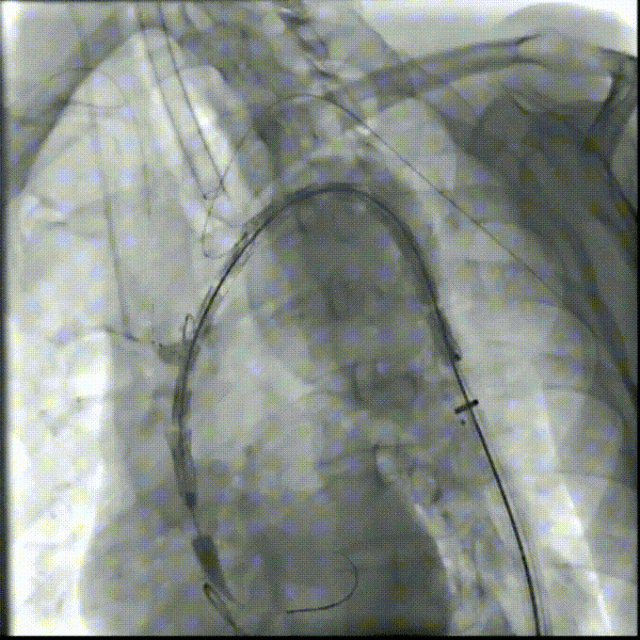

2. 主体支架释放

通过预弯外鞘将主体支架送至主动脉弓,拔除鞘管,向无名动脉拉入单分支支架

鞘内预置的4F导管帮助超选LSA,建立LSA通路(逆行性通道)

释放主体支架

3. 分支支架植入

左颈总动脉建立通路后,将分支支架系统送入朝前的内嵌分支通道中释放(顺行内通道)

在已建好的LSA通路中释放分支支架